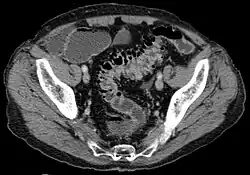

- Contrast CT is the investigation of choice in acute episodes of diverticulitis and where complications exist.